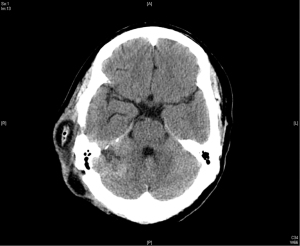

The patient recovered well after the surgery. However, a follow up image in March 2010 revealed a focal small recurrent tumor over the original surgical tumor bed (Figure 2). Due to the recurrence, patient underwent radiotherapy as stereostatic radiosurgery (SRS) with a dose of 14 Gy in one fraction in May 2010, achieving a good response. He was tumor free for the next 5 years.